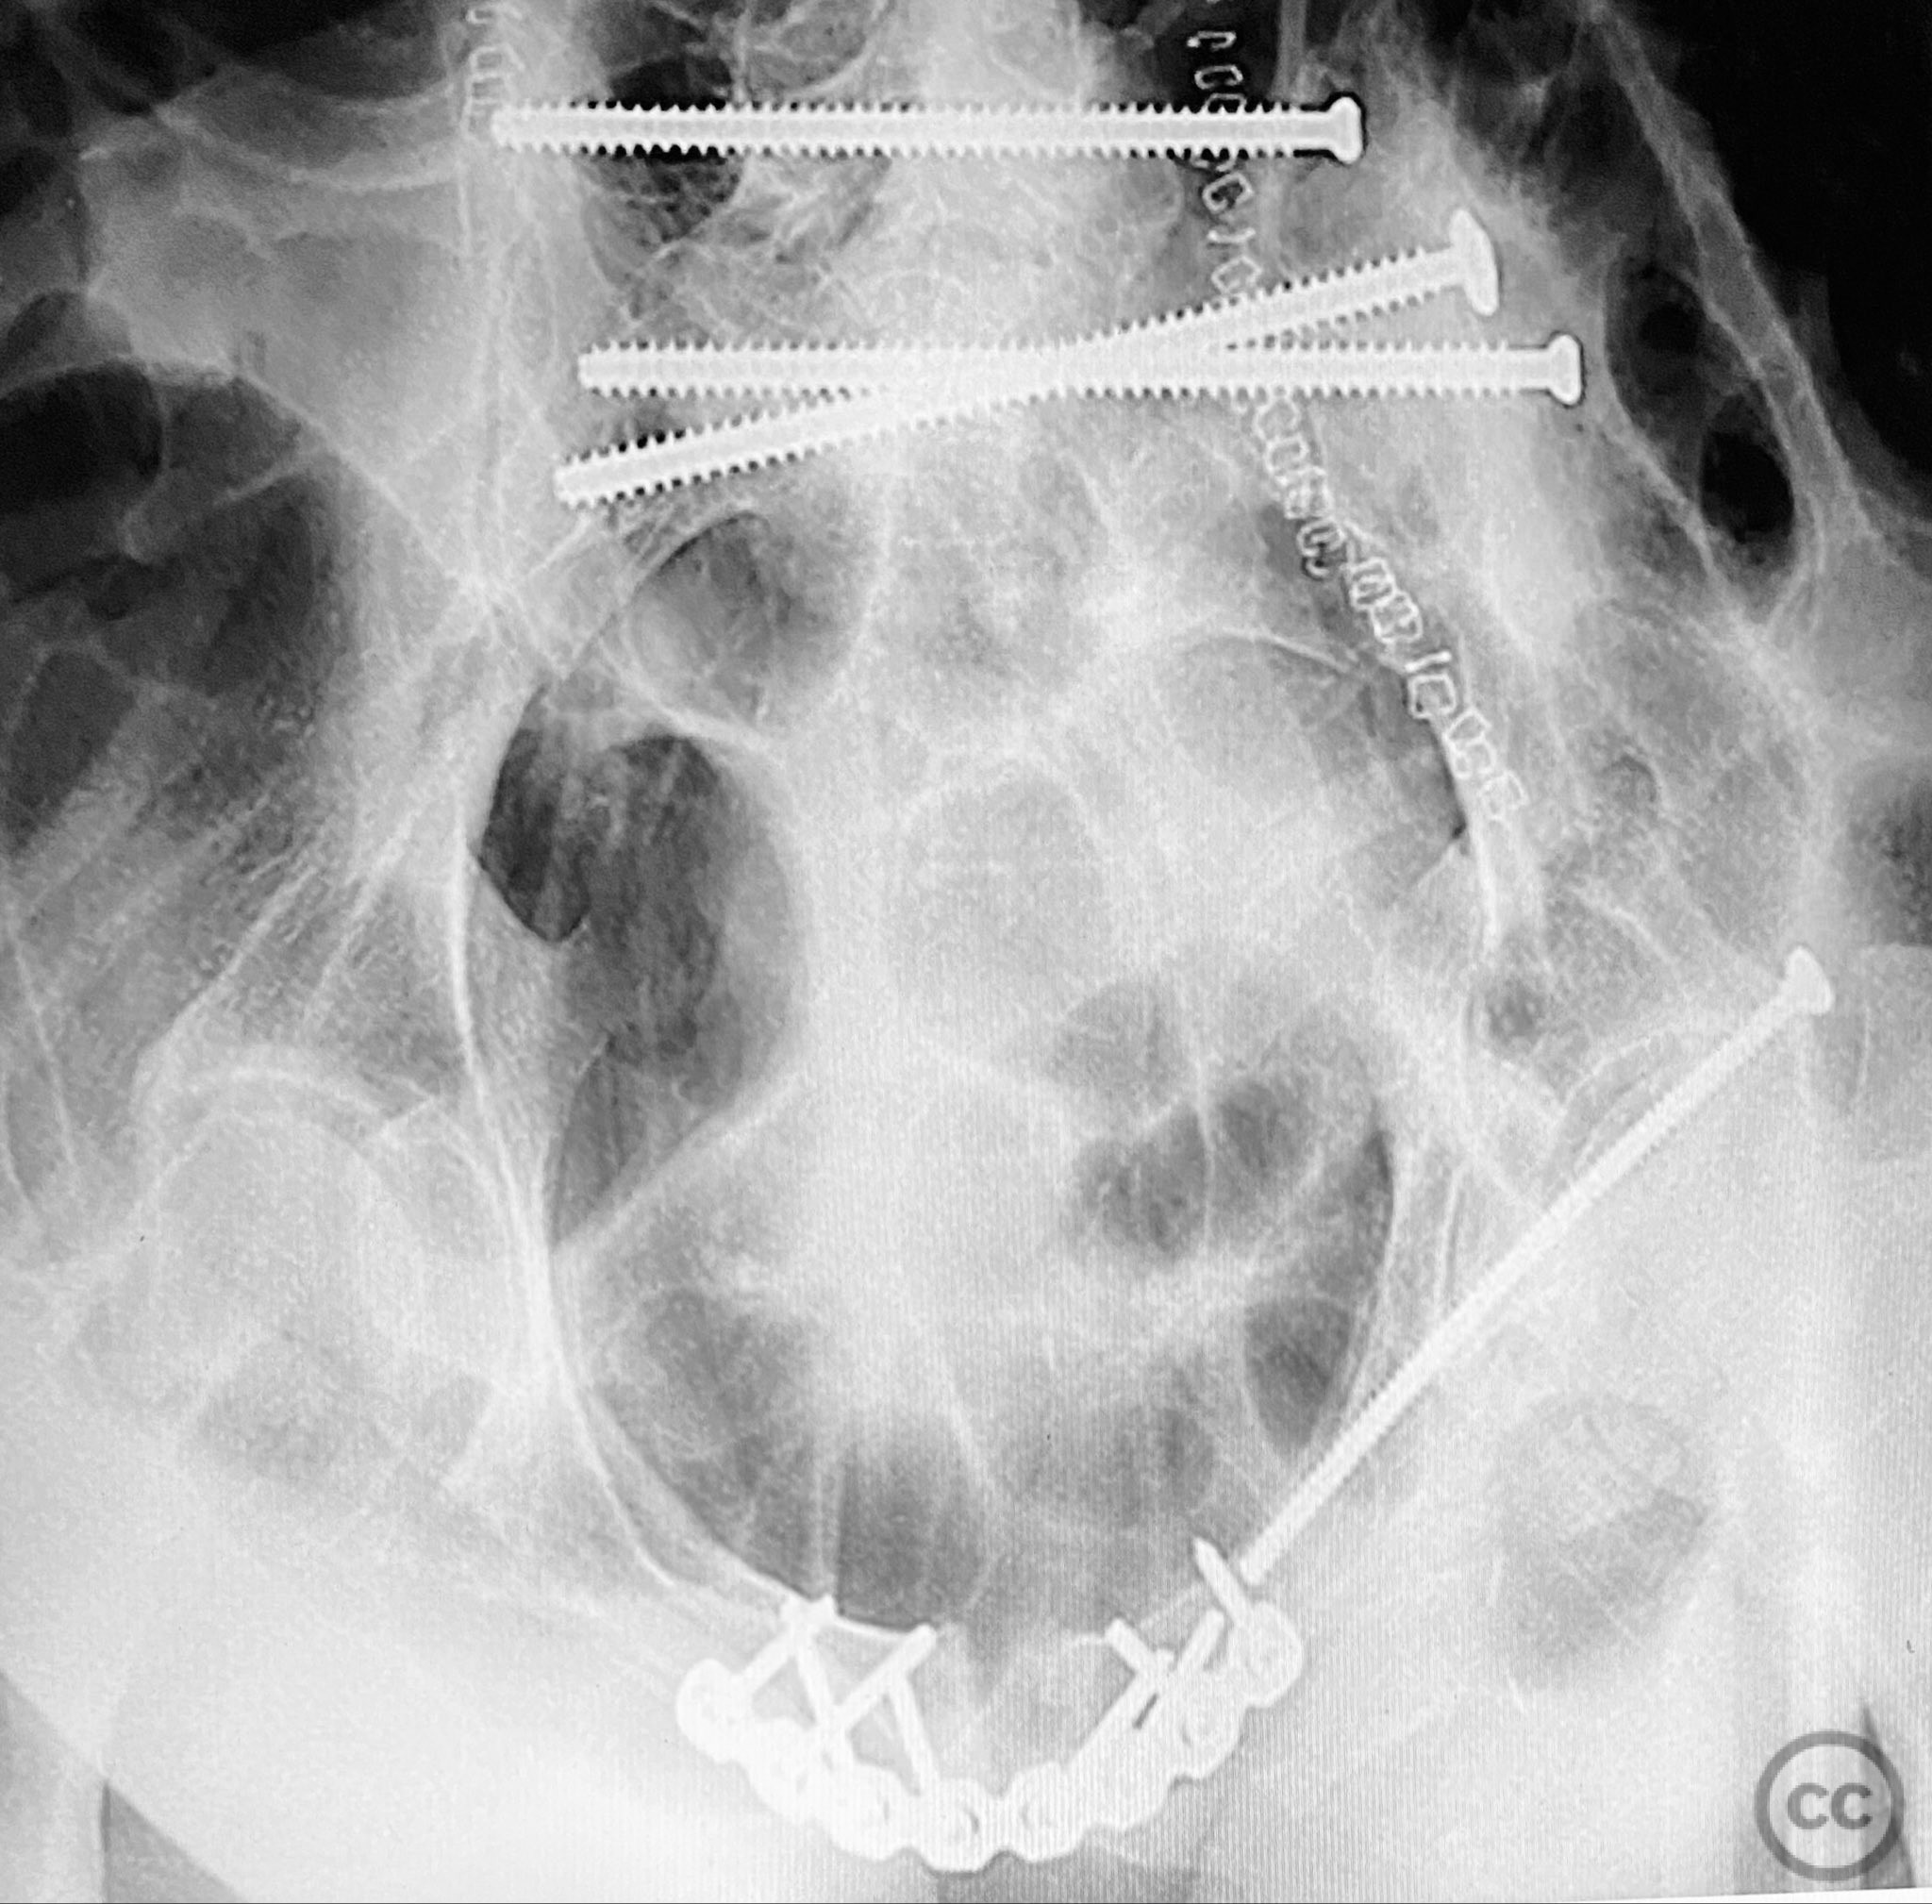

Anatomical surgical approach:  Posterior approach to the sacrum via a midline longitudinal incision, subperiosteal dissection to expose the dorsal sacral cortex and fracture lines. Direct reduction of the sacral fragments using clamps applied to the dorsal cortical edges, with intraoperative fluoroscopic guidance. Placement of iliosacral screws (non-cannulated, <130mm length due to implant availability at the time) across S1, supplemented by a posterior transiliac screw. For anterior fixation, a Pfannenstiel incision was used to expose the symphysis pubis and superior pubic rami; reduction achieved with pointed reduction forceps, followed by plate osteosynthesis of the symphysis and screw fixation of the rami as indicated.

The staged approach allowed direct assessment and refinement of posterior reduction using dorsal cortical landmarks, which was critical given the comminution and displacement pattern. The absence of long cannulated screws limited optimal iliosacral screw placement; screws were contained within the osseous fixation pathway but not ideally positioned for maximal safety or precision by contemporary standards. Anterior ring stabilization was performed after confirming satisfactory posterior reduction on postoperative CT. The sequence addressed both vertical and rotational instability, but implant limitations may have increased risk for suboptimal fixation or neurovascular compromise. In current practice, advanced imaging, navigation, and longer cannulated screws would be utilized to optimize screw trajectory and safety.

Postoperative protocol:   Early mobilization with protected weight bearing for 8-12 weeks, depending on radiographic evidence of healing and clinical stability. Thromboprophylaxis until full mobilization. Progressive physiotherapy focusing on core stability and hip range of motion.

Orthopaedic implants used:   6.5mm non-cannulated iliosacral screws (<130mm), posterior transiliac screw, anterior symphyseal plate, cortical screws for pubic rami